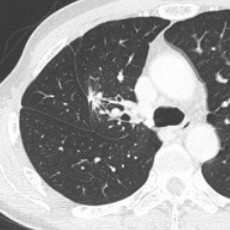

呼吸器外科領域

O-arm2 一例として、触知不能肺腫瘍であるすりガラス状結節に対して、位置の把握のためにO-armを使い、手術中に撮像することにより、より精度の高い手術が行えるようになりました。

- 術前

- 術中

- 術後